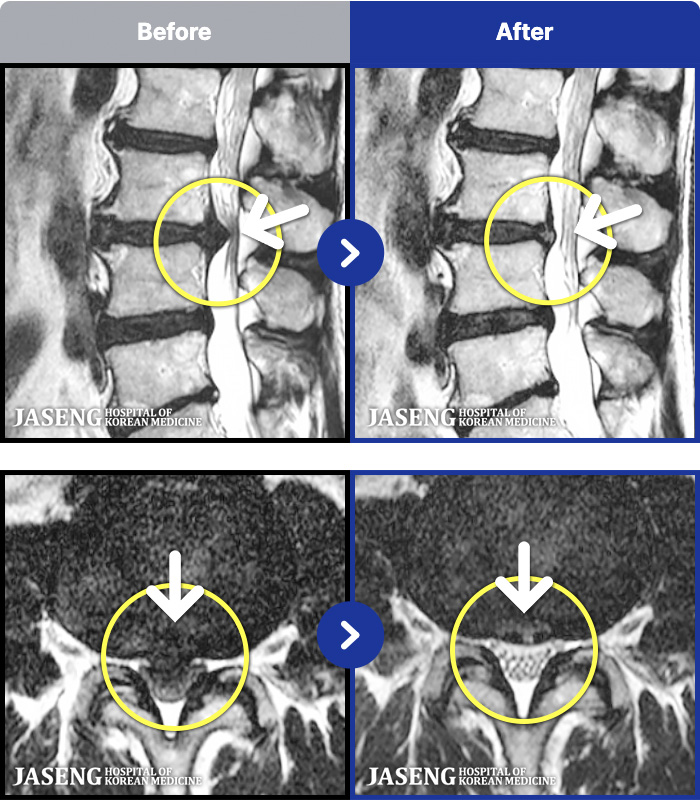

- MRI ġ

MRI ġ

1,299 MRI ũ ʸ Ȯϼ.